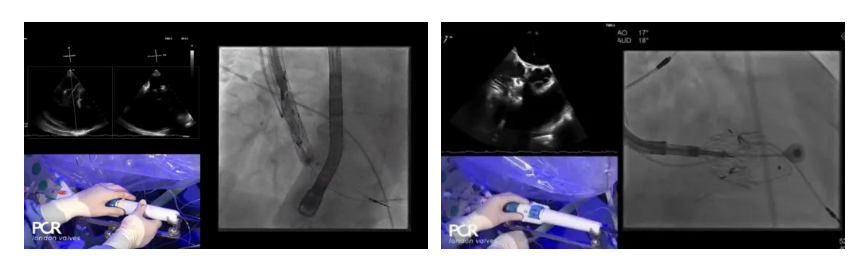

手術(shù)在全麻狀態(tài)下開(kāi)展,采用經(jīng)右側(cè)頸靜脈入路的方式將輸送器送入患者心臟內(nèi),在TEE及DSA引導(dǎo)下調(diào)整輸送器頭端角度,使得輸送器與三尖瓣瓣環(huán)平面垂直。在輸送器進(jìn)入右心室后釋放室間隔錨定裝置,而后釋放瓣葉夾持件(2個(gè)耳片結(jié)構(gòu))成垂直狀態(tài)。在TEE及DSA確定夾持件固定至三尖瓣葉根部且位于右室側(cè)后釋放人工瓣心房側(cè)盤(pán)片。隨后調(diào)整瓣膜同軸性以及室間隔錨定件位置(貼合室間隔),前推藏針管并固定,進(jìn)而釋放室間隔錨定裝置,并再次確認(rèn)瓣膜位置、穩(wěn)定性及同軸性,合攏輸送鞘后撤出輸送器,完成LuX-Valve Plus人工三尖瓣瓣膜的植入。